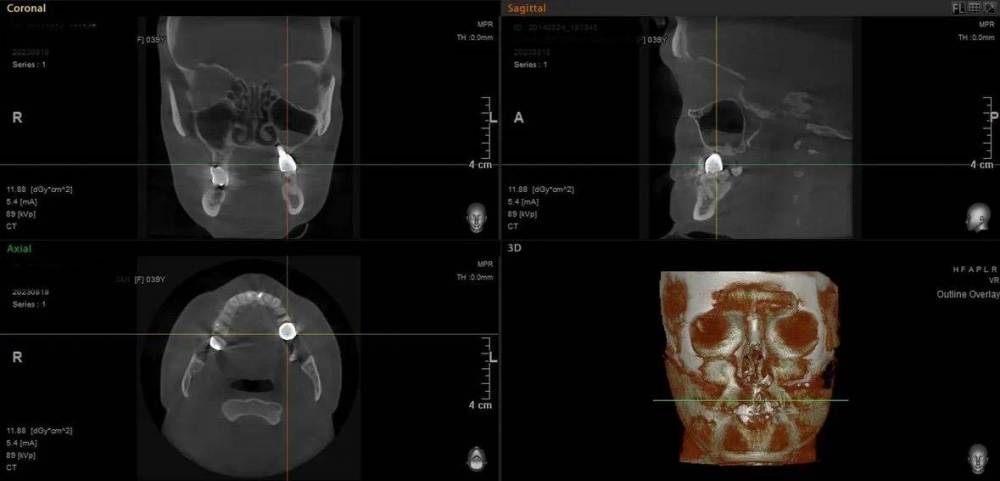

Mitt Опубликовано 29 октября, 2023 Поделиться Опубликовано 29 октября, 2023 (изменено) Здравствуйте. Ж., 39 лет. Так получилось, что мне нужно решить, что делать с имплантатом на месте верхней шестерки. А тк я не обладаю необходимой компетенцией, очень нуждаюсь в подсказках специалистов. Дано: 1. 2014-2015 гг - удаление зуба, синус лифтинг, имплантация с пластикой мягких тканей, установка коронки. 2. 2015 - 2019 гг - проблема контактов с рядом находящимися пятым и седьмым зубами, воспаление десны вокруг 5, имплантант, 7. Решалось путем композитных «накладок» на 5 и 7 зубы. 3. 2019 - 2023 гг - пластика мягких тканей, удаление 7 зуба с подсыпкой графта, еще штуки 3 или 4 пластики, включая вестибулопластику, временная коронка. 4. 2023 г - установка новой постоянной коронки, 5 месяцев тишины, с августа гной в районе имплантата (десна спокойна). Проблемы общие для всех временных периодов - тандем с пазухой и периодические ближе к постоянным боли разной интенсивности и локации (пазуха, 7 зуб, место от 7 зуба, стенка носа, кость), мне сложно лоцировать( Мне нужно выбрать, что делать дальше: попробовать почистить имплантат, или уже отпустить=удалить. Вариант почистить и еще сделать пластику пока не рассматриваю, тк после стольких пластик частичная парастезия неба. Может быть, кто-то подскажет, к какому решению в итоге прийти.. P.s. Я не знаю , какие скрины кт нужны( кт 08.2023 Изменено 29 октября, 2023 пользователем Mitt Ссылка на комментарий